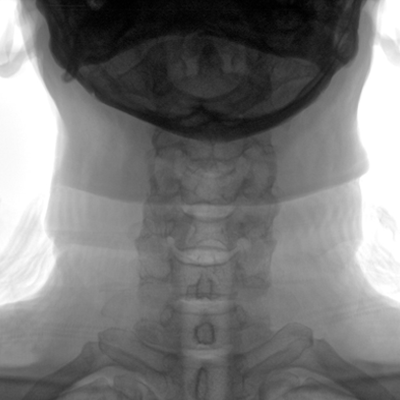

大尺寸動(dòng)態(tài)平板探測(cè)器,高DQE、低噪聲、圖像清晰。采用多分辨率圖像增強(qiáng)處理技術(shù),不同部位不同圖像處理算法,滿足客戶多樣化的需求。

多角度自由旋轉(zhuǎn),滿足患者復(fù)雜擺位需求。